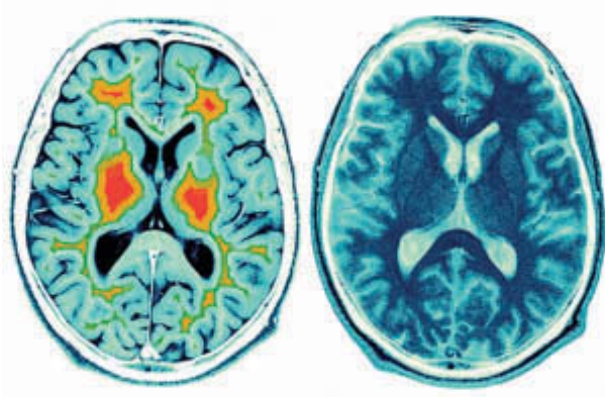

• Reduced levels of cortisol – the stress hormone

• Improved blood flow and electrical activity in their brains